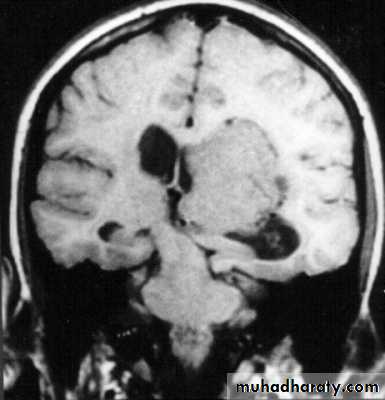

Skull X-ray findings in increased intracranial pressure

• Sutural separation in children.

• ‘Copper-beating’ marking of the cranial vault.

• Thinning of dorsum sellae.

• Erosion of the posterior clinoid process.

Copper-beating’ marking

Neurosurgery